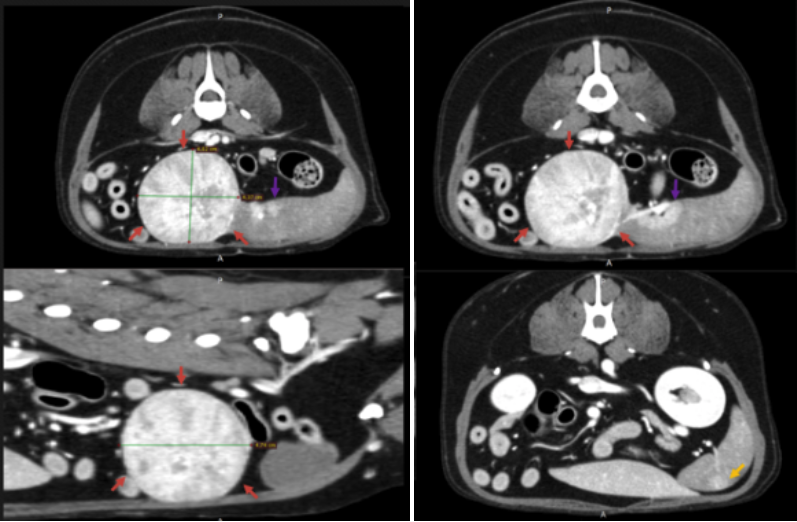

정확한 진단을 위해 본원에서 CT 검사를 진행하였습니다.

강아지 비장종양 CT 검사 결과 / 출처: 에스동물메디컬센터

CT 주요 소견

비장 꼬리 부분에서 4.4 x 4.0 x 3.5cm 크기

둥글고 경계가 뚜렷한 종괴 확인

내부는 이질적이며 조영제에 뚜렷하게 반응

이 혹은 비장종양, 조혈기능 과다, 림프조직 증식 등 가능성

​주변 비장 조직에도 작은 병변 등이 관찰되어 조직검사 권장

​인근 림프절이 약간 커져 있었으나(3.8mm),

염증 반응인지 전이 가능성인지는 불분명